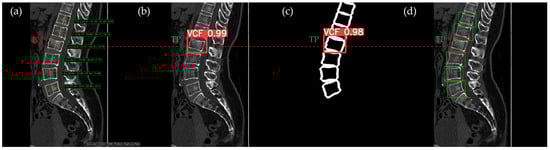

Figure 10, Figure 11, Figure 12, Figure 13 and Figure 14 illustrate typical examples of results for HLR, EEVD, TSVD_SD, and TSVD_DC in patients with acute VCFs. The results of applying different methodologies to the same patient image and identical slice locations were as follows. In the HLR results, each vertebra was marked with yellow solid lines indicating the height measurement lines for the anterior, middle, and posterior regions. The measured height values and HLR percentages were displayed on the right side of the image. If the HLR percentage ranged between 25% and 40%, it was highlighted in orange, while values of 40% or higher were highlighted in red. In the EEVD results, the VCF detection outputs were displayed along with their respective confidence scores based on the input patient images. For the TSVD_SD results, after performing spine segmentation, the model extracted only the spine contour, and the VCF detection results with their corresponding confidence scores were presented. In the TSVD_DC results, bounding boxes were generated for each vertebral body, with normal vertebrae represented in green and vertebrae identified as VCFs displayed in red.

In Figure 13, the L1 vertebra was normal, whereas a VCF was present at the L2 level. This patient exhibited irregular cortical endplate appearances from T11 to L2. Radiological evaluation concluded that there was an acute VCF only at the L2 level, which the HLR method failed to detect. However, all convolutional neural network (CNN)-based methods—EEVD, TSVD_SD, and TSVD_DC—successfully detected the VCF at L2 by extracting and analyzing specific features of spinal images. In TSVD_DC, there was an additional FP, as the model incorrectly identified a VCF at L1.

Figure 13. The VCF detection results from four different methods. (a) HLR, (b) EEVD, (c) TSVD_SD, and (d) TSVD_DC. The acute VCF, as confirmed by the radiologist, was located at the L2 level. TP, TN, FP, and FN were marked at the same level with a red dotted line. The HLR was low at L2, which was the reason for the FN in (a). The L1 vertebra was misclassified as VCF by TSVD_DC.